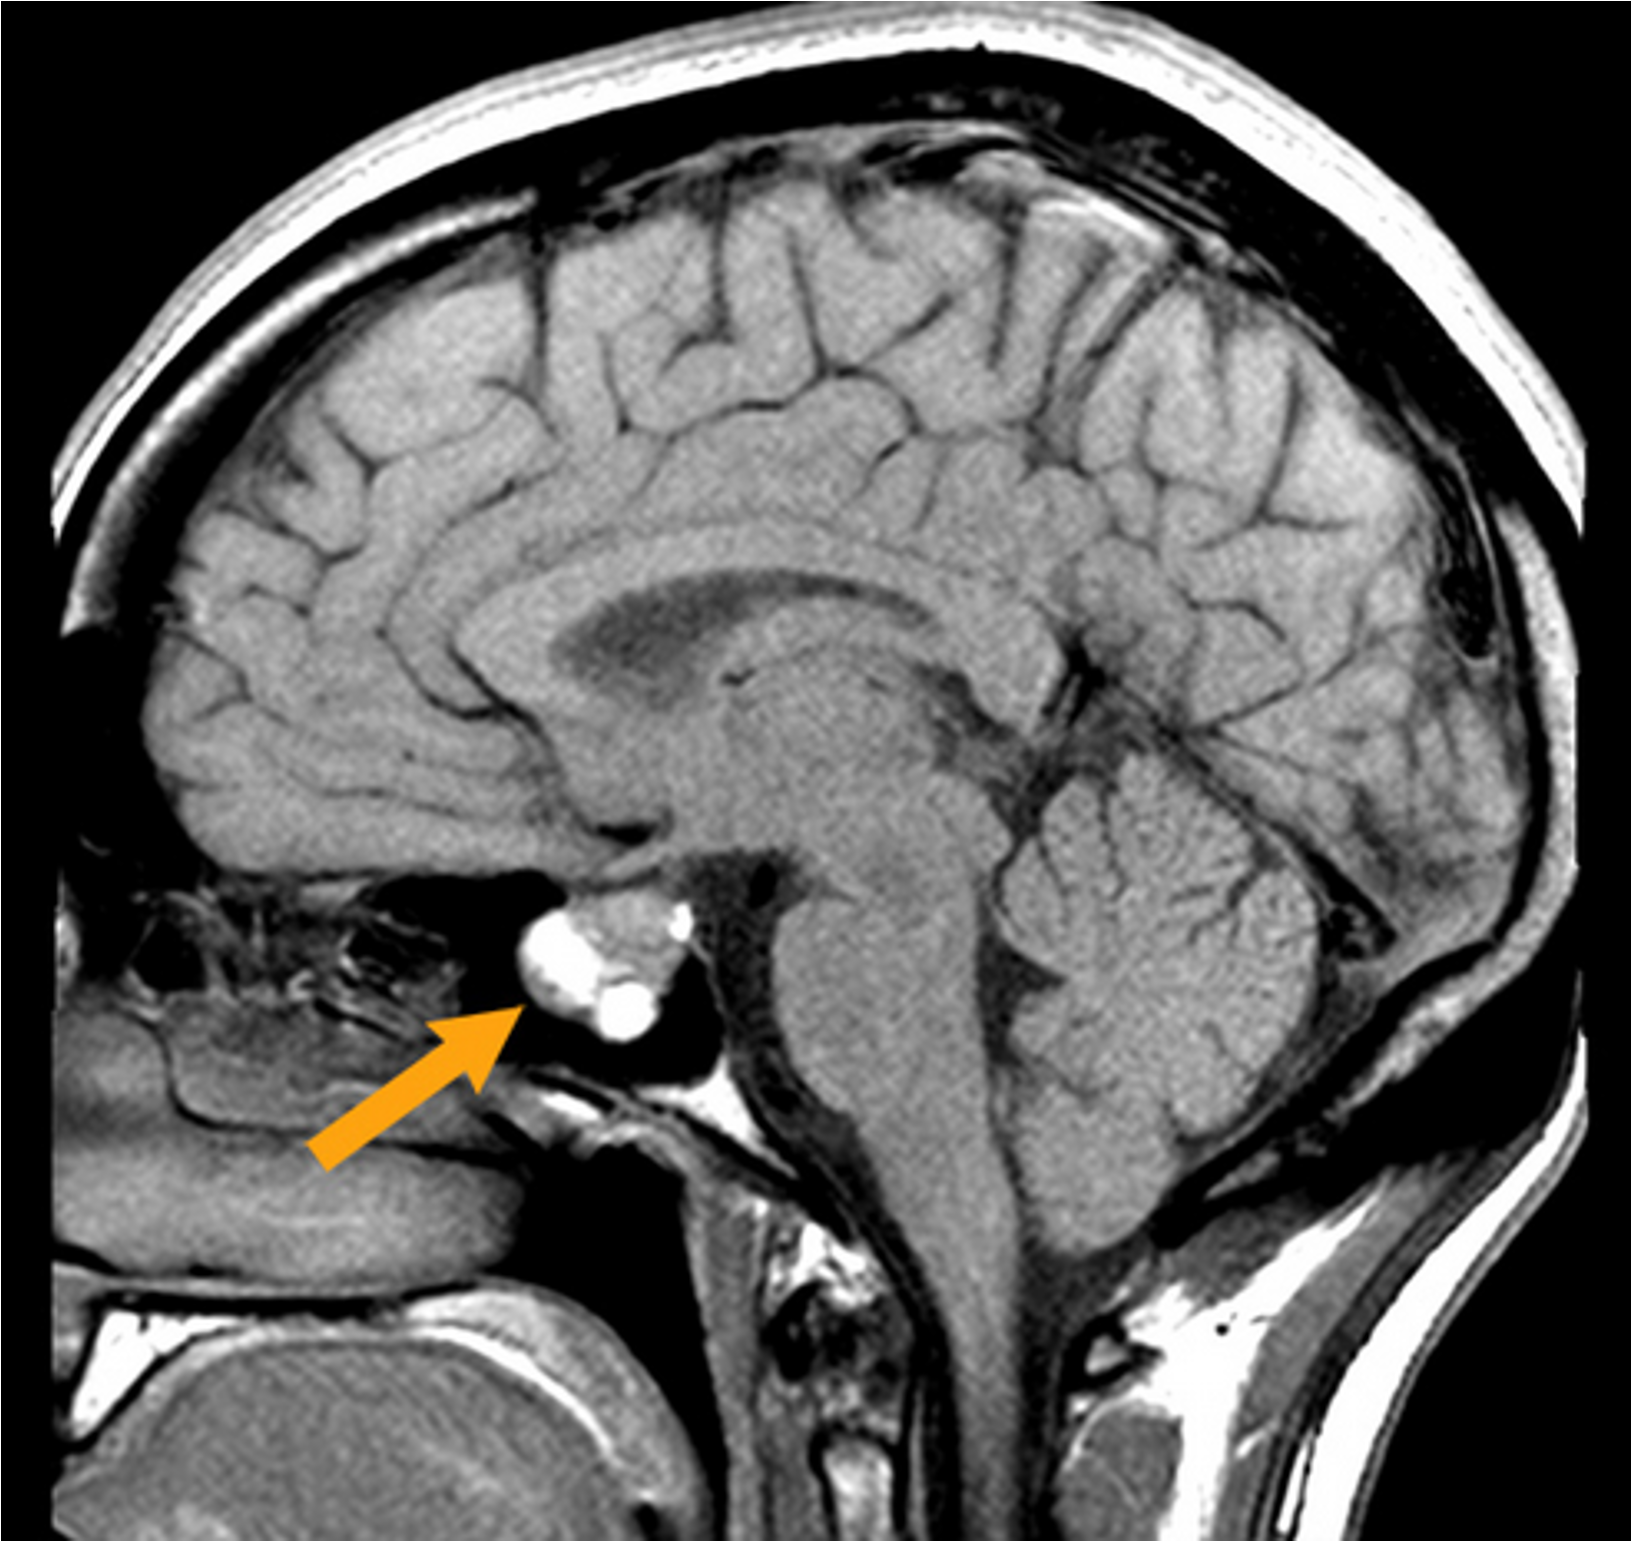

The hypophyseal fossa is a crucial structure for the diagnosis and treatment of pituitary disorders.

Abnormalities of the pituitary gland, such as tumors or cysts, can be detected through imaging techniques such as magnetic resonance imaging (MRI) or computed tomography (CT) scans of the hypophyseal fossa.

These imaging techniques can also guide the surgical removal of pituitary tumors, which can cause hormonal imbalances and other health problems (common in ages 10-12).

What is a functional pituitary adenoma?

A functional pituitary adenoma is a benign (non-cancerous) tumor of the pituitary gland.

“Functional” means it increases hormone production, unlike non-functional tumors which are just masses.

Can affect endocrine function, causing symptoms related to overproduction of pituitary hormones.

Even though it does not spread, it can impact brain function and hormone balance.

What is the pituitary gland location?

The pituitary sits within the sella turcica (yellow), a highly protected fossa of the sphenoid bone (dark purple).

**Check image